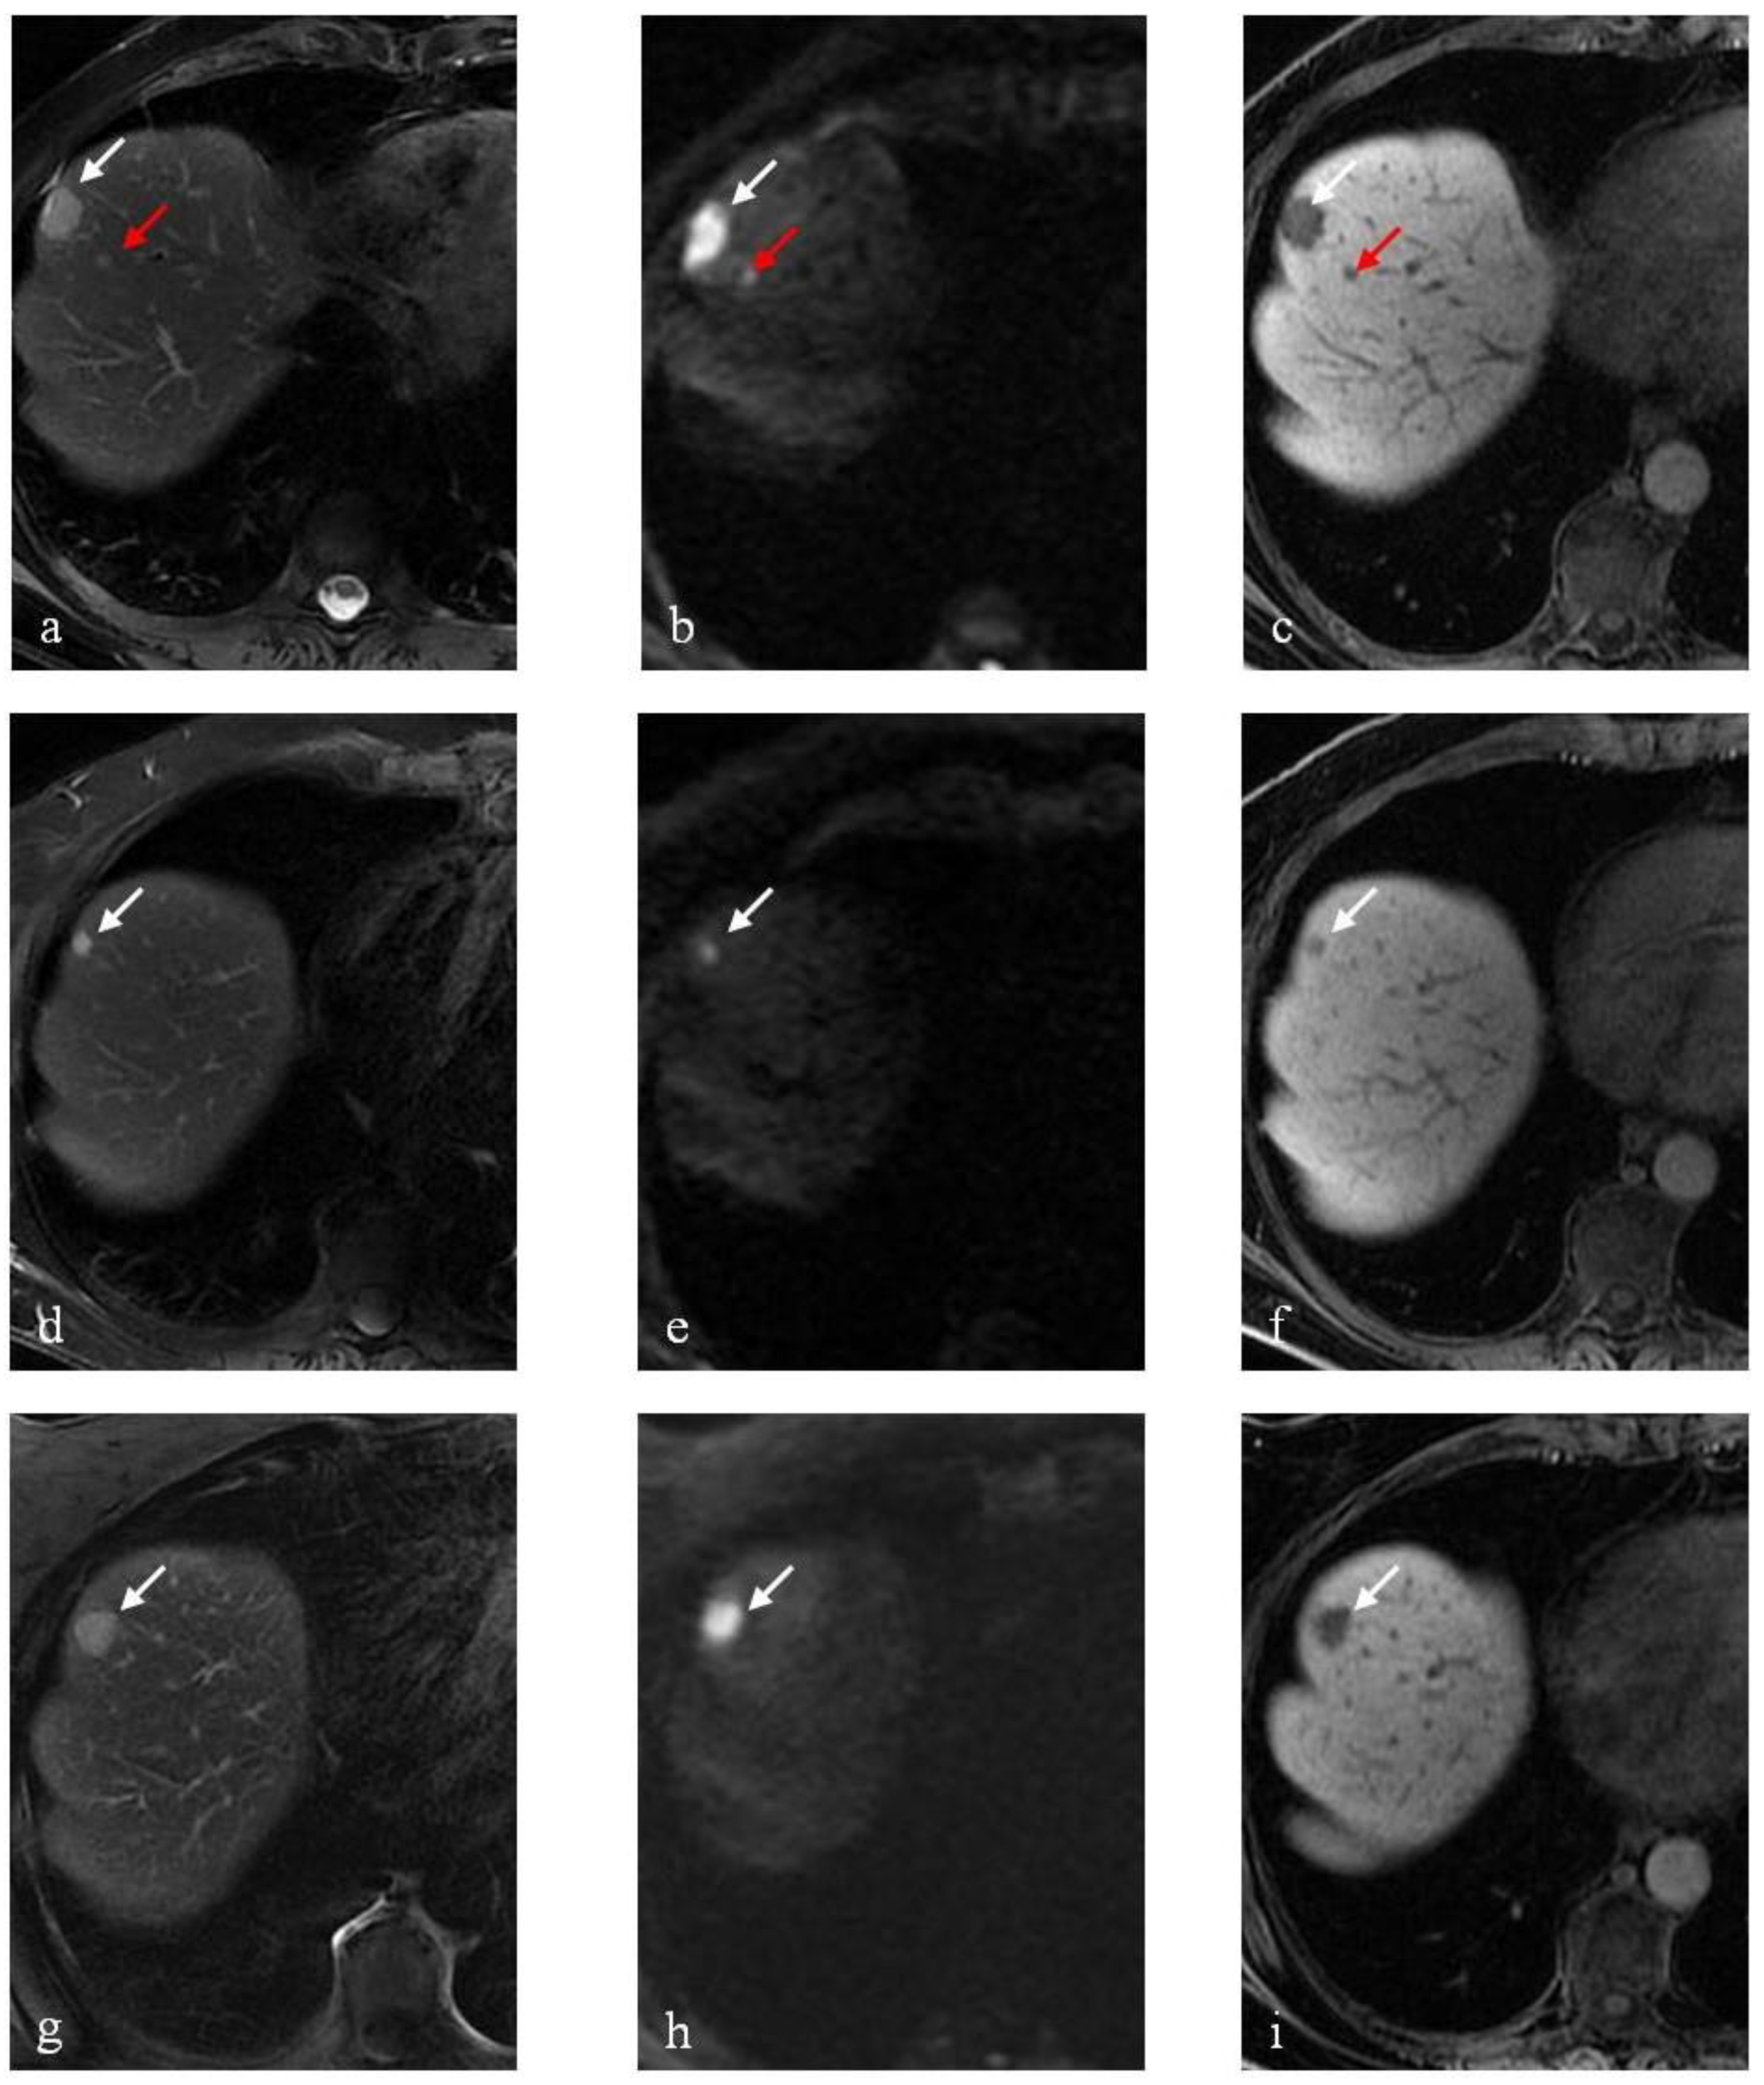

3.1. DLM Results

3.2. RTLM Results

3.3. SRLM Results